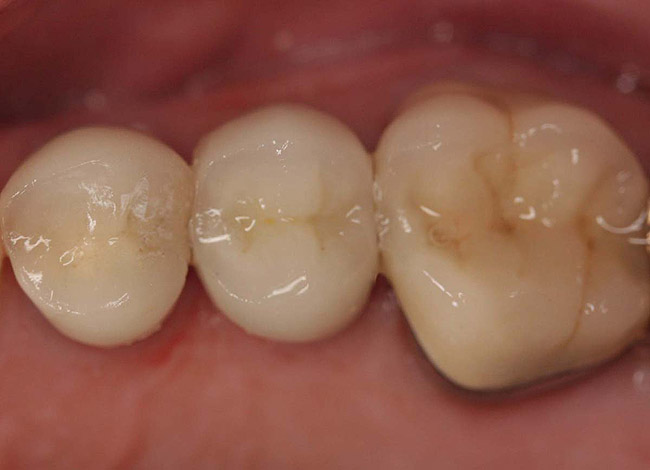

Figure 11  Final porcelain-fused-to-metal crown.

Figure 11

Core build-up was completed with Absolute Dentin™ (Parkell, www.parkell.com) dual-cure high-strength core composite. There are variations on color and how materials cure. For example, Light-Core™ (Bisco, www.bisco.com) is a light-cured blue material, Encore® (Centrix, www.centrixdental.com) is a self-cure white material, and Para Core (Coltène Whaledent, www.coltene.com) is a dual-cure white or dentin-colored material. Material was placed directly and light-cured for 40 seconds (Figure 9). Final preparation for a PFM was completed (Figure 10). The final crown was placed (Figure 11).